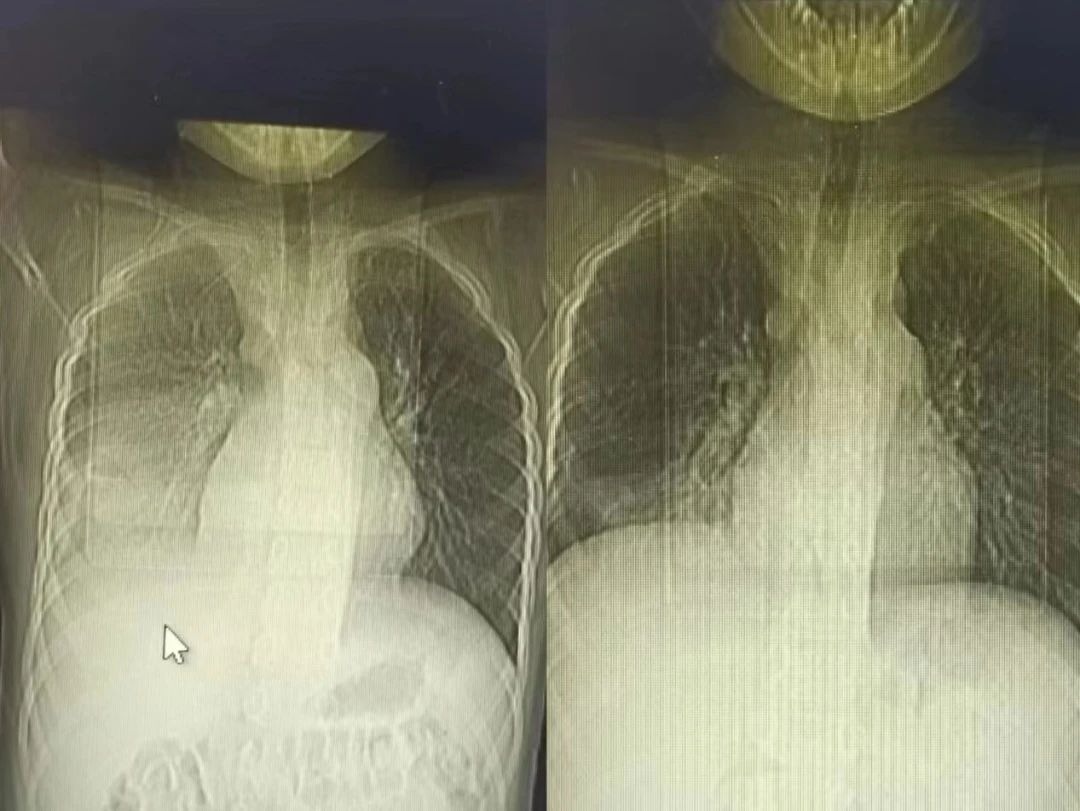

半个多月前,一名9岁的小男孩七七在父母的陪伴下,来到了锦州市妇婴医院(妇幼保健院)小儿呼吸科。因为反复高热、咳嗽10天,辗转于外院治疗6天,病情却逐渐加重,反复39-40度不退,复查的肺CT提示重症肺炎。

节假日期间,七七出现了间歇性胸痛,疼出了眼泪,又出现了一次低热,家属的心再一次提到了嗓子眼儿。刘铁英主任连忙赶到医院看望他,担心重症肺炎可能出现恢复期的肺栓塞,又紧急联系放射线,放射线曹主任马上安排会诊给他急查了肺增强CT。结果出来后没有发生栓塞,医护人员和家属都松了一口气,考虑跟胸水吸收后引起的胸膜牵扯痛有关系,对症处置后2-3天胸痛消失,发热也很快消失。